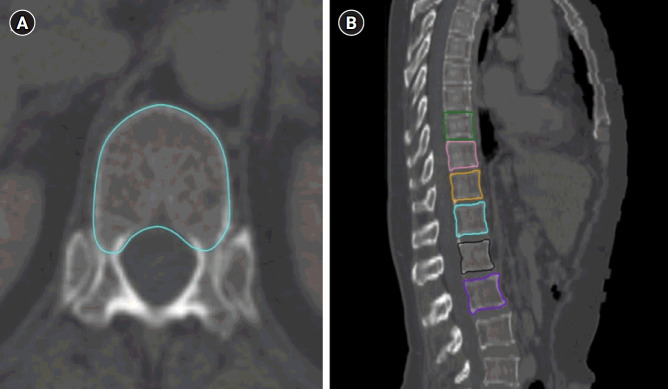

Materials and methods: We retrospectively analyzed the data of 271 patients with non-metastatic GC who received adjuvant RT between 2010 and 2020. The vertebral bodies from 9th thoracic (T9) to 2nd lumbar (L2) were contoured in computed tomographies used for RT planning, and V30, V35, V40, mean doses, and HUs of vertebrae were documented. We conducted univariate and multivariate analyses to identify the risk factors for VCF development.